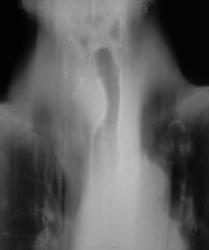

Пациентка направлена из Т.О. с диагнозом хронический бронхит на рентгенографию ОГК.

что подобная демонстрация уже была и коллеги выдвигали версию о загрудинном зобе? Необходима  правая боковая  рентгенограмма. С уважением Nik

Загрудинный  зоб при данной единичной рентгенограмме наиболее вероятен. Но и хронический бронхит отрицать не буду. Хотелось бы боковой снимок.

Бокового нет, не делали, а, вот, "томки" имеются. Сейчас загружу.

Вроде всё так. Но УЗИ здесь информативнее: Структуру узла увидели бы и связь со щитовидной железой.

Опухольсредостения.